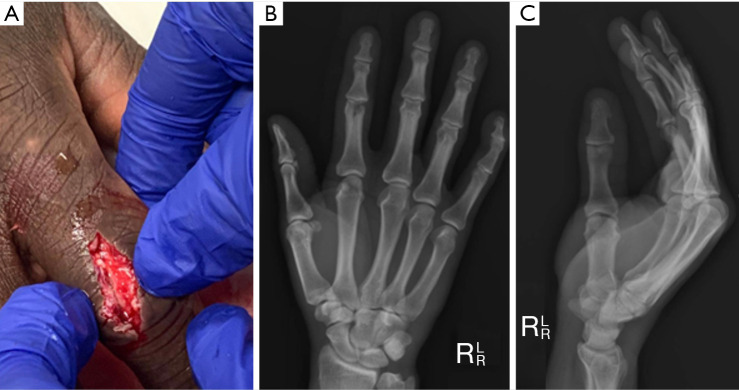

Case description: This case report highlights the successful treatment of a severe PIP joint fracture-dislocation in a 49-year-old male carpenter who sustained a traumatic laceration to the right index finger. The injury's complexity led to the pioneering use of an osteochondral autograft from the patient's second toe proximal phalanx, marking a novel approach in autologous tissue utilization for joint reconstruction. This method effectively achieved fracture resolution and joint stabilization. A comprehensive literature search was conducted up to May 2024 across multiple databases, including PubMed, Embase, Cochrane Library, Scopus, and Web of Science. The search strategy employed a combination of Medical Subject Headings (MeSH) terms and keywords related to PIP joint fracture-dislocations and osteochondral autografts. Inclusion criteria were articles in English involving human subjects, focusing on osteochondral autografts for PIP joint fracture-dislocations. Exclusion criteria included studies involving animals or cadaveric models and those not focused on osteochondral grafts. Postoperative assessments of the patient revealed successful graft integration and notable recovery in finger mobility, alongside positive functional hand outcomes as confirmed by patient-reported measures.

Conclusions: The significant enhancements in structural and functional aspects highlight the potential of this technique. Despite its sparse representation in the literature, the favourable outcomes of this case strongly support further exploration of using second toe proximal phalanx osteochondral autografts. This report underscores the need for extensive, prospective research to comprehensively ascertain the method's effectiveness and safety in addressing intricate PIP joint fracture dislocations.